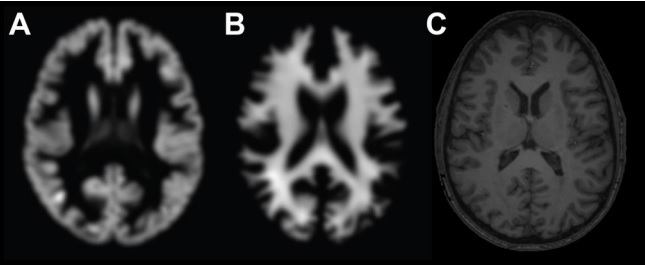

Пример нейровизуализации входных данных для использования в моделях прогнозирования возраста. А — серое вещество в осевой проекции, В — белое вещество в осевой проекции, С — «сырые» или минимально обработанные Т1-взвешенные изображения.